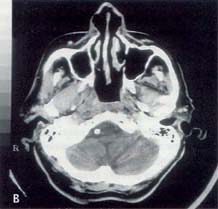

Εικόνα

2. Καρκίνος του ρινοφάρυγγα πριν (Α) και μετά (Β) τη θεραπεία με

ακτινοβολία.